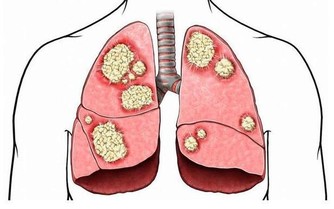

6、揪揪嗓:預防半夜咳嗽

有一些上了年紀的人,常常白天不咳夜裡咳,這有可能是肺虛。建議晚飯時喝點百合枸杞粥或荷葉花生粥,滋陰潤肺效果非常不錯。

另外,晚上睡前不妨揪一揪嗓子。揪嗓子跟刮痧是一個道理,但是因為脖子上的皮膚細嫩,血管敏感,自己刮痧的話,力度或位置把握不准容易出危險。揪一揪很方便,而且效果也很不錯。